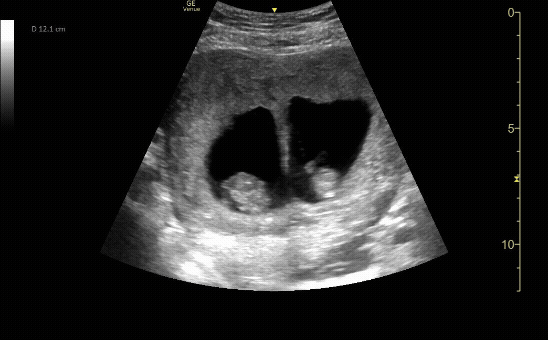

Transverse view of the uterus with twin gestation at 10-12 weeks.

c/o Ala’a Abu-Spetani, MD